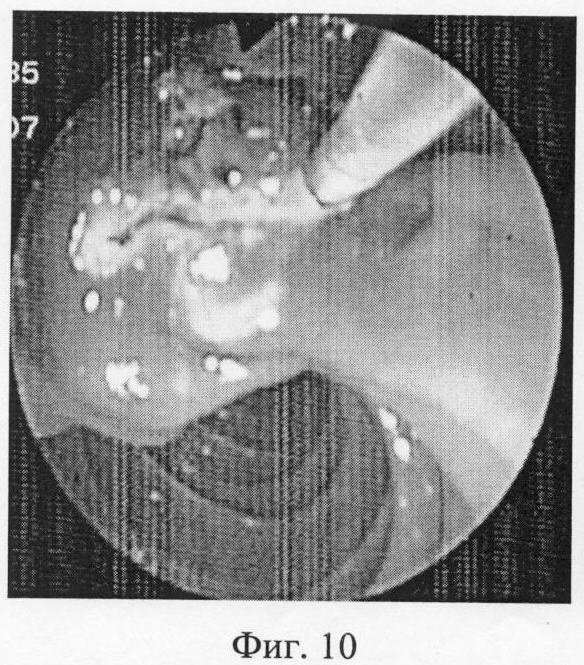

Фиг.10 – после углубления продольного разреза осуществлен доступ в подслизистые слои, однако доступ в общий желчный проток не удается. Производится поперечный разрез слева направо.